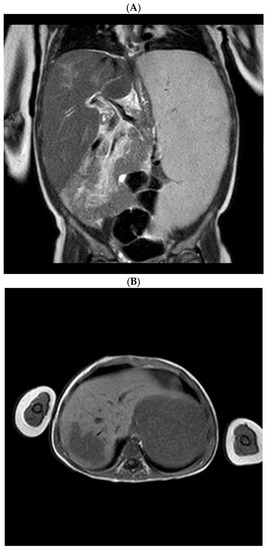

Radiological assessment of the visceromegaly was performed: computed tomography (CT) and magnetic resonance imaging (MRI) described the massive splenomegaly and highlighted a hepatic focal lesion (Figure 1).

Figure 1. Magnetic resonance imaging shows massive splenomegaly and hepatomegaly (A), with a focal hepatic lesion characterized as gaucheroma (B).